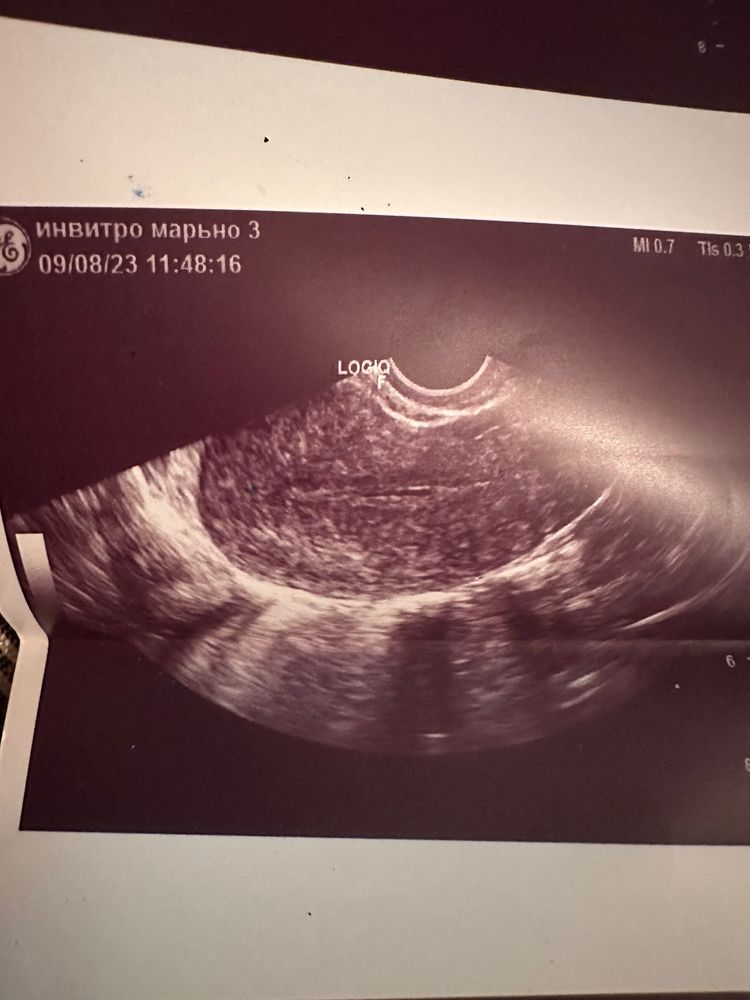

Второй цикл, 6 день - узи, эндометрий 3 мм, ДФ нет.

В матке определяется жидкость, расширена до 1 см. Вот само узи и фото этой фигни в матке. Уверили, что не гематометра и не полип.